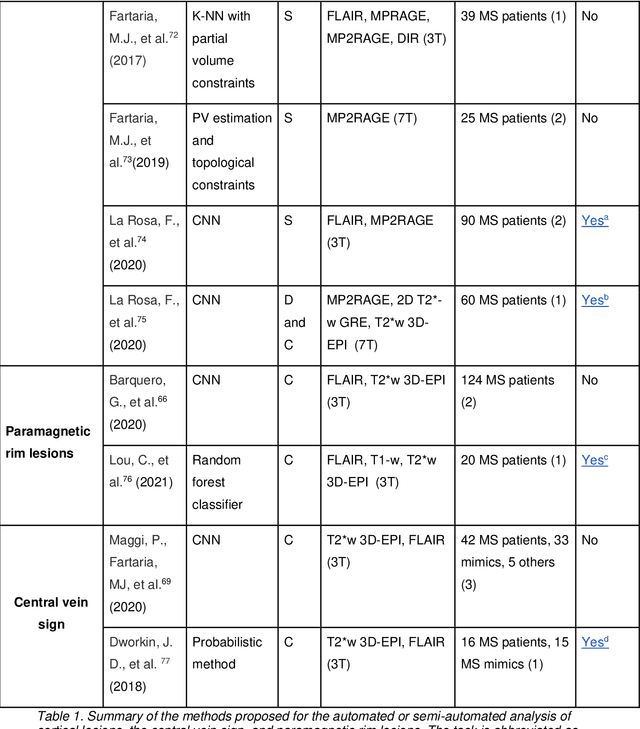

Abstract:The current multiple sclerosis (MS) diagnostic criteria lack specificity, and this may lead to misdiagnosis, which remains an issue in present-day clinical practice. In addition, conventional biomarkers only moderately correlate with MS disease progression. Recently, advanced MS lesional imaging biomarkers such as cortical lesions (CL), the central vein sign (CVS), and paramagnetic rim lesions (PRL), visible in specialized magnetic resonance imaging (MRI) sequences, have shown higher specificity in differential diagnosis. Moreover, studies have shown that CL and PRL are potential prognostic biomarkers, the former correlating with cognitive impairments and the latter with early disability progression. As machine learning-based methods have achieved extraordinary performance in the assessment of conventional imaging biomarkers, such as white matter lesion segmentation, several automated or semi-automated methods have been proposed for CL, CVS, and PRL as well. In the present review, we first introduce these advanced MS imaging biomarkers and their imaging methods. Subsequently, we describe the corresponding machine learning-based methods that were used to tackle these clinical questions, putting them into context with respect to the challenges they are still facing, including non-standardized MRI protocols, limited datasets, and moderate inter-rater variability. We conclude by presenting the current limitations that prevent their broader deployment and suggesting future research directions.